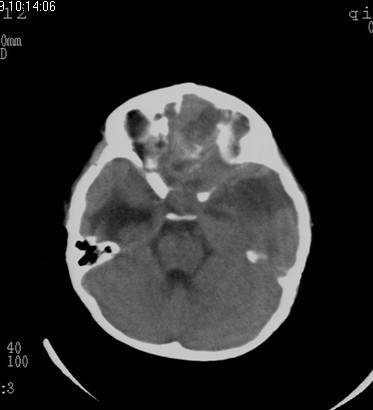

男  4岁  家长觉得反应迟钝来检查发现。

病史?脑疝都形成了,这家长也太马虎了。

感冒后发现反应迟钝来检查

考虑脑占位并出血,脑疝形成。

考虑左侧颞顶叶占位并出血,脑疝形成

有出血,考虑神经母细胞瘤或星形细胞瘤,胶母好发老年人,儿童罕见,中颅窝的是扩大的侧脑室颞角吧不是囊肿吧。脑白质密度减低,建议mr.

先天性疾病.小脑是正常的,左侧大脑半球发育不良伴有脑肿瘤形成,脑积水.名堂真多。建议mri

考虑左侧颞顶叶占位并出血,脑疝形成!

考虑左侧颞顶叶占位并出血,脑疝形成!梗阻性脑积水

考虑左侧颞顶叶占位并出血,脑疝形成,梗阻性脑积水。

1)考虑左侧额颞顶叶肿瘤并卒中;建议行进一步检查。2)大脑镰下疝,左侧颞叶沟回疝。3)脑积水(梗阻性)。

支持考虑左侧颞顶叶占位并出血,脑疝形成,梗阻性脑积水。

左侧颞顶叶占位并出血,脑疝形成

考虑左侧额颞顶叶占位并出血,脑疝形成,梗阻性脑积水。